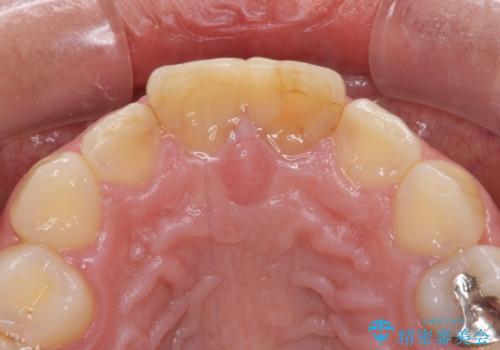

- 前歯の形と色を気にして来院された患者様です。

虫歯で神経を取り除いたことによる変色や充填物の着色などが認められたため、オールセラミッククラウンにて補綴することとしました。

また、咬耗により周囲の歯がすり減ったことで、前歯2本のみが長く見えていたため、周囲に長さを合わせることとしました。